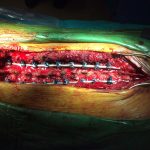

Η διόρθωση της παραμόρφωσης της σπονδυλική στήλης έγινε δια οπισθίας προσπελάσεως με την χρήση:

α) Νευροπαρακολούθησης

β) Συστήματος ελέγχου ακριβούς τοποθέτησης των κοχλιών εντός των σπονδυλικών σωμάτων (O – Arm)

Εικ. 3 Σύστημα πλοήγησης O – Arm για την διεγχειρητική τοποθέτηση των κοχλιών εντός των σπονδυλικών σωμάτων